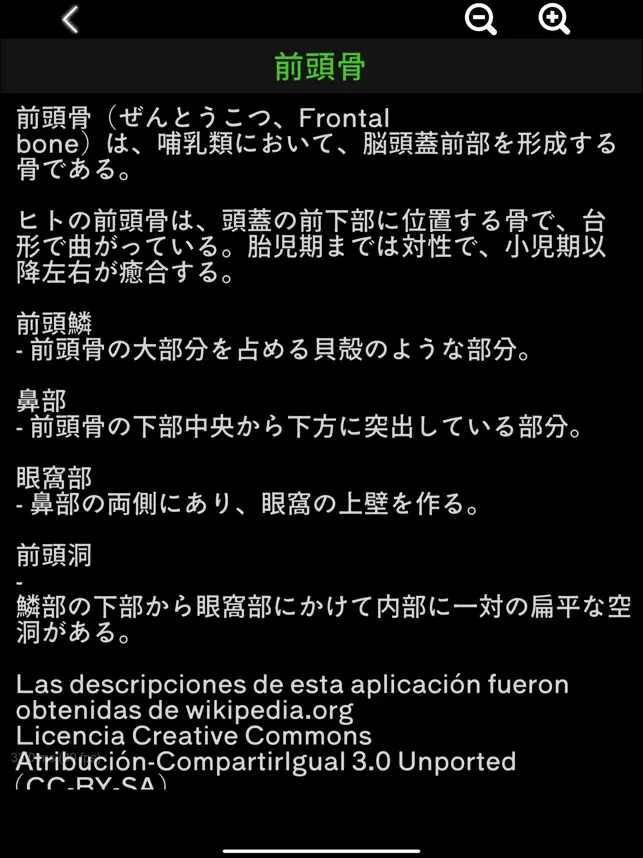

骨システムの 3 次元モデルとそれらすべての説明が表示されます。

頭蓋骨、背骨、肋骨、胸骨、大腿骨、脛骨、腓骨などの各骨を触るとその情報が表示されます。